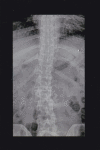

Figure 3

Anteroposterior radiograph showing mild lumbar scoliosis.